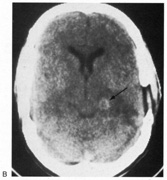

Cerebral blindness is distinguished from ocular disease by both normal pupillary light responses and normal fundoscopic examination. These may lead to an erroneous diagnosis of factitious visual loss. Associated signs of damage to parietal or temporal structures help to confirm cerebral blindness but may not always be present. Visual evoked potentials are of limited diagnostic value. They can be altered voluntarily by subjects without visual loss67 and can be normal in patients with striate lesions.68,69 They cannot differentiate between blind and seeing children with neurologic disease,70 and normal or abnormal results do not predict visual outcome.60,71 Absent evoked responses are rare and may only occur early in the course.70 Absent alpha rhythm on electroencephalography72,73 is reportedly a more sensitive diagnostic sign than abnormal visual evoked potentials.60 CT scans can be normal, but modern MR imaging with coronal images through the occipital lobe should reveal most striate or optic radiation lesions with complete and persistent visual loss (Fig. 16). Single photon emission computed tomography (SPECT) scans may reveal bilateral functional defects in cases with unilateral MRI lesions.74

Fig. 16. CT scan of man with cerebral blindness after a gunshot wound.